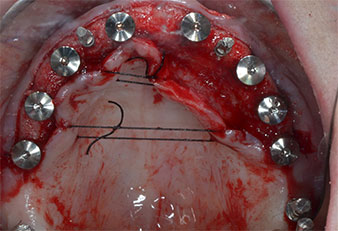

Compte tenu de la dureté relative de l’os (D2) à cet endroit, les sites recevant des implants de 10mm de long aux régions 11 et 21 ont été finalisés à l'aide d’une fraise de 4mm de diamètre, associée à un contre-angle chirurgical W&H WS-75 L, au moteur d'implantologie Implantmed de W&H ainsi qu’au module Osstell ISQ de W&H. En revanche, en raison de leur structure osseuse molle, les sites postérieurs ont été préparés en vue de l’obtention d’un diamètre final de 3mm à l'aide de l’insert Piezomed I3P. Les implants ont enfin été posés par voie transgingivale (Flap Less) pour obtenir l’ostéointégration dans un délai de trois mois (Figures 6-10). L'appareil existant a été maintenu sur quatre implants provisoires (Fig. 8).

Implant de 10mm au niveau du tissu

Fig. 6 : Un implant de 10mm au niveau du tissu est placé en région 21. L’implant en région 11 et les trois implants postérieurs gauches de 4mm sont déjà en place.

Stabilité des implants

Fig. 7 : La stabilité de l’implant est déterminée à l’aide d’un SmartPeg et du module W&H Osstell ISQ. Toutes les valeurs sont situées dans la plage moyenne à haute, avec une valeur minimale de ISQ 69.

Implants provisoires

Fig. 8 : Après la fixation des façonneurs gingivaux, des implants provisoires sont posés en régions 18, 12, 22 et 28.